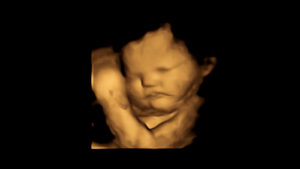

A study led by Durham University’s Fetal and Neonatal Research Lab, UK, took 4D ultrasound scans of 100 pregnant women to see how their unborn babies responded after being exposed to flavours from foods eaten by their mothers.

Fetuses exposed to carrot showed more “laughter-face” responses while those exposed to kale showed more “cry-face” responses.

Facial reactions seen in both flavour groups, compared with fetuses in a control group who were not exposed to either flavour, showed that exposure to just a small amount of carrot or kale flavour was enough to stimulate a reaction.